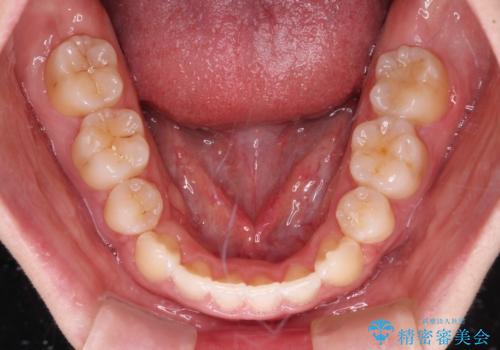

骨格的に下顎骨が前方位にあるため、口元の突出感改善には限界があると思われましたが、唇の閉じにくさが改善するほど引っ込めることができました。